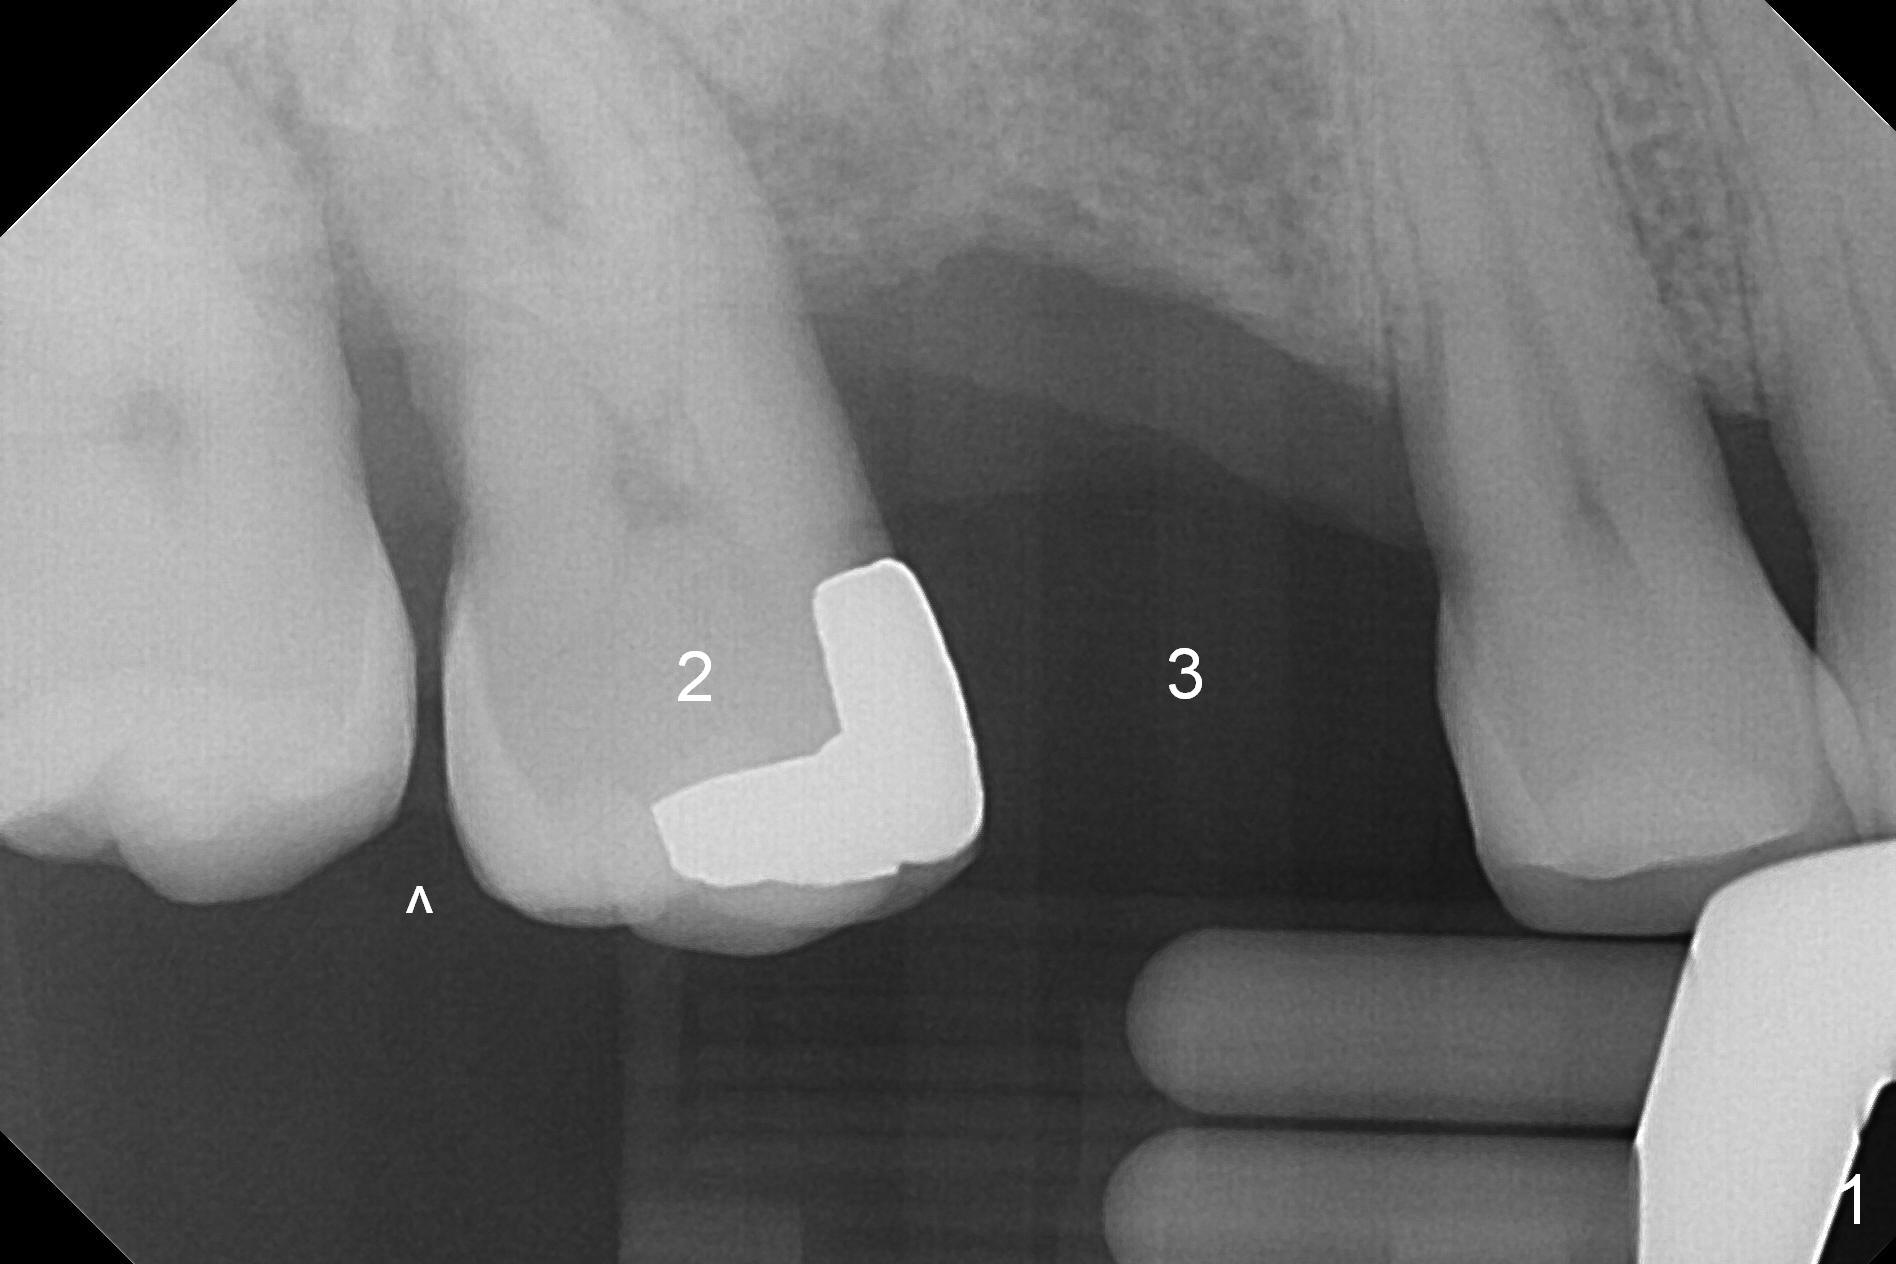

A 53-year-old man wants treatment so that the tooth #2 will not have the fate of the tooth #3. It appears that etiology includes periodontitis and occlusal trauma (Fig.1, 2). The tooth #2 has shifted mesially (Fig.1 ^). The initial drill of DIO Sinus Lift Master Kit will be used for 6 mm (Fig.2), followed by round burs for 7 mm or more. Place PRF and allograft (Metronidazole) before implant placement.